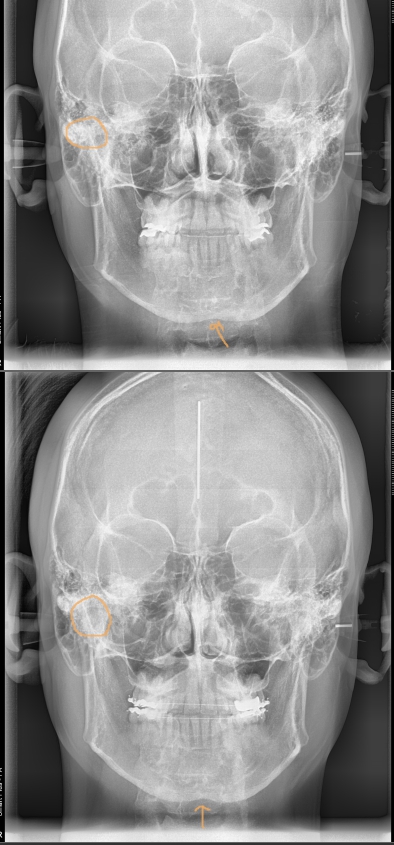

모든 환자에서 그런것은 아니지만, 어떤 비대칭의 경우에는 치성으로 이러나는 경우도 있습니다. 본 환자분의 경우 치성으로 약간의 중심선 안맞음과 비대칭이 발생하였고, 치성간섭을(치아가 먼저 부딪혀서 생기는 아래턱의 틀어짐) 없애주었더니 자연스럽게 어느정도 비대칭이 개선된 것을 확인 할 수 있었습니다. 모든 비...

이것을 진단하기 위해 엑스레이 사진을 찍고, 턱관절을 확인하며, 치아중심선도 확인하며 본을 떠서 치아 교합을 확인하기도 합니다.